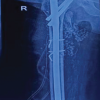

A 27-year-old man BMI of 22.7 kg/m2 came to the clinic with complaints of pain and instability of his left knee. He had a history of fall from motorbike 14 months prior and was diagnosed with fracture of the LTC. Review of his injury investigations showed that he had an osteochondral fracture of the posterolateral tibia as seen of plain radiographs and CT scan. Open reduction and fixation of the fracture with two K-wires was performed through a posterolateral approach (Fig. 3). On examination, there was valgus alignment and he walked with an antalgic gait and valgus thrust. Tenderness was present posterolaterally, range of motion was 0–120° with Grade 3 valgus laxity and Lachman test Grade 3.

The primary treatment of the patient had already been performed elsewhere and his presenting symptoms included instability and continuous pain in his knee. The plan was to correct his malalignment and treat medial and anterior knee instability. The planning for this deformity correction was done using TraumaCad® (BrainLab, Munich, Germany) software. The anatomic medial proximal tibia angle was 89°, lateral distal femur angle was 85°, and hip knee axis was 184°. It was decided to correct the valgus alignment by a distal femur osteotomy because the coronal alignment of tibia was normal, and an osteotomy at this level would have tilted the joint line. Arthroscopy was performed, which revealed full-thickness cartilage loss of the posterolateral tibial condyle and loss of lateral meniscus tissue (Fig. 8).